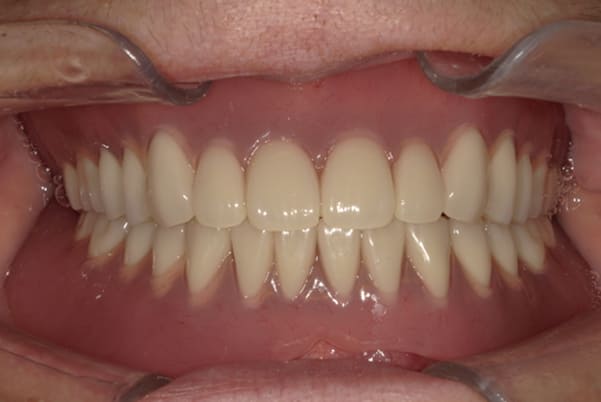

症例レポート[CASE.05]

食事ができるようになりたい

- 性別・年齢

- 女性(40代)

- 主訴

- 食事ができない、何とかしたい

- 治療

-

- 上顎精密金属床総入れ歯

- 下顎精密金属床総入れ歯

- 治療期間

- 約6か月間

- 費用

- 上顎精密金属床総入れ歯:55万円

- 下顎精密金属床総入れ歯:55万円

合計:110万円(税込)

奥歯がなくなり、放置されたことで、かみ合わせが深く乱れた状態でした。

乱れたかみ合わせを治し、治療途中で見た目は患者様がご納得いく、歯の大きさ、色、形をご一緒に確認しながら入れ歯を最終的に作製しました。

上顎治療後

下顎治療後